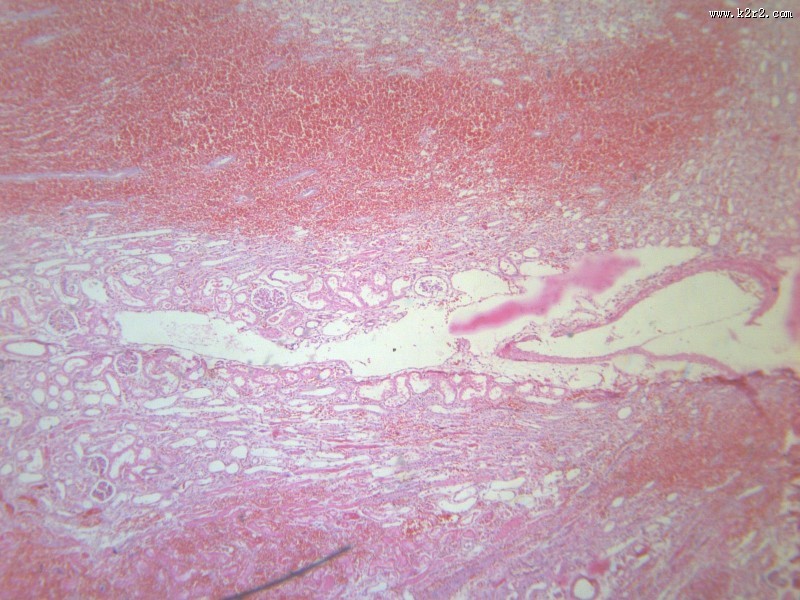

> 肾小管坏死 第5张

肾小管坏死 - 第5张

肾小管坏死

肾凝固性坏死

肾小管水肿

医学

显微切片